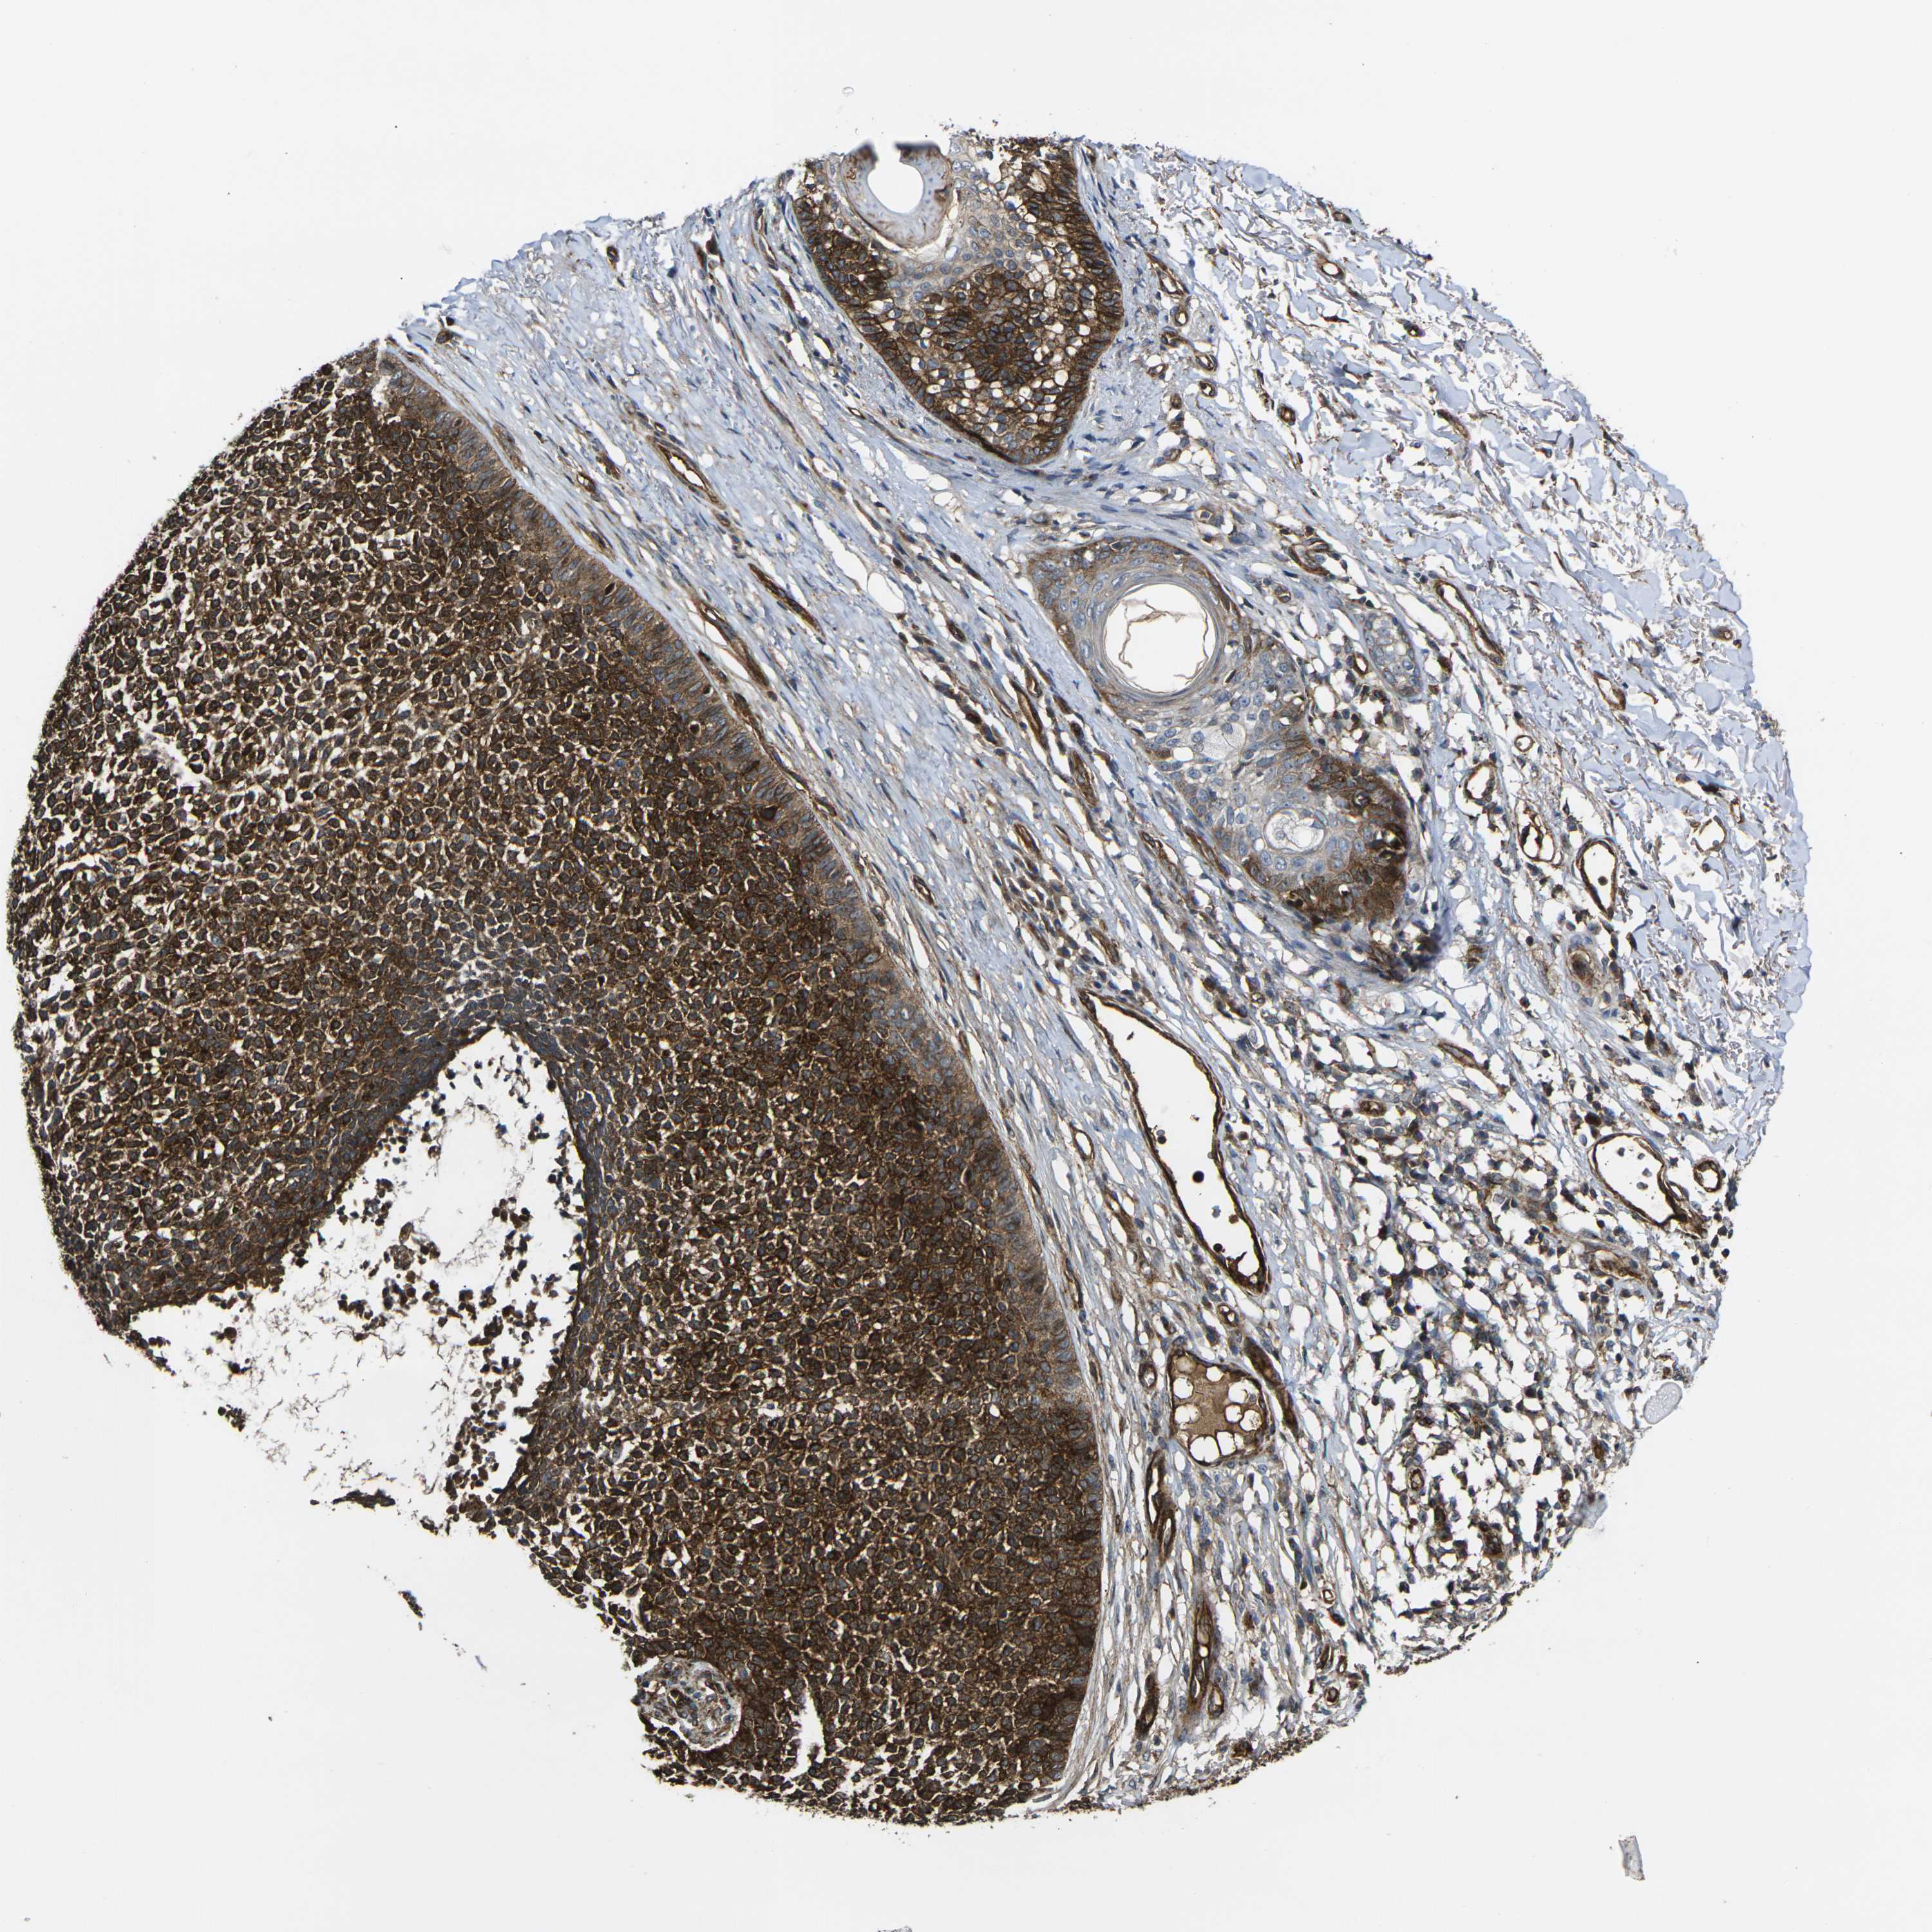

Basal cell and squamous cell cancer

SKIN CANCER - Protein expressioni

A mouse-over function shows sample information and annotation data. Click on an image to view it in a full screen mode. Samples can be filtered based on level of antibody staining by selecting one or several of the following categories: high, medium, low and not detected. The assay and annotation is described here.

Antibody stainingi

Antibody staining in the annotated cell types in the current human tissue is reported as not detected, low, medium, or high, based on conventional immunohistochemistry profiling in selected tissues. This score is based on the combination of the staining intensity and fraction of stained cells.

Each image is clickable and will lead to virtual microscopy that enables deeper exploration of all samples and also displays staining intensity scores, fraction scores and subcellular localization as well as patient and tissue information for each sample.

Antibody HPA001490

Antibody HPA013616

Staining

High

Medium

Low

Not detected

Intensity

Strong

Moderate

Weak

Negative

Quantity

>75%

75%-25%

<25%

None

Location

Nuclear

Cytoplasmic/membranous

Cytoplasmic/membranous,nuclear

Squamous cell carcinoma, NOS

Basal cell carcinoma